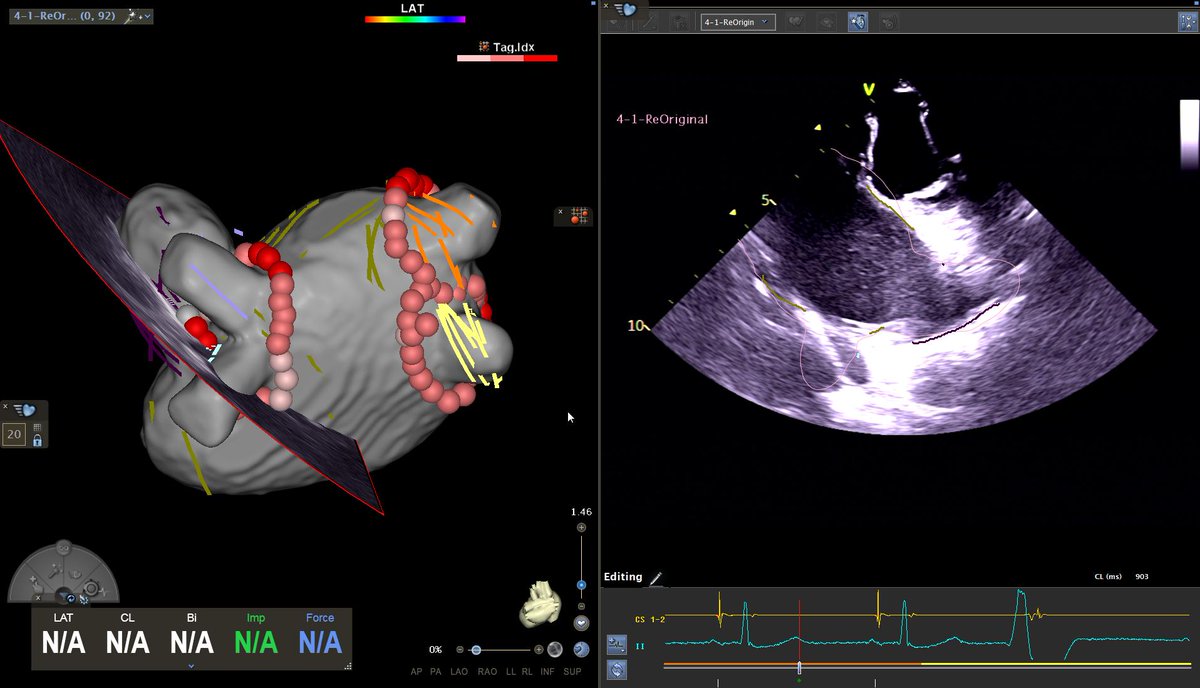

Interesting focal AT in our first Live Course as a Biosense Center of Excellence, with 4 seconds of RF to termination. As usual, ICE making our life easier. Looking forward to our next session!

@BiosenseWebster @EpCardiac @JustoJuli1 @SimonJewell10 @AlexBarbour6